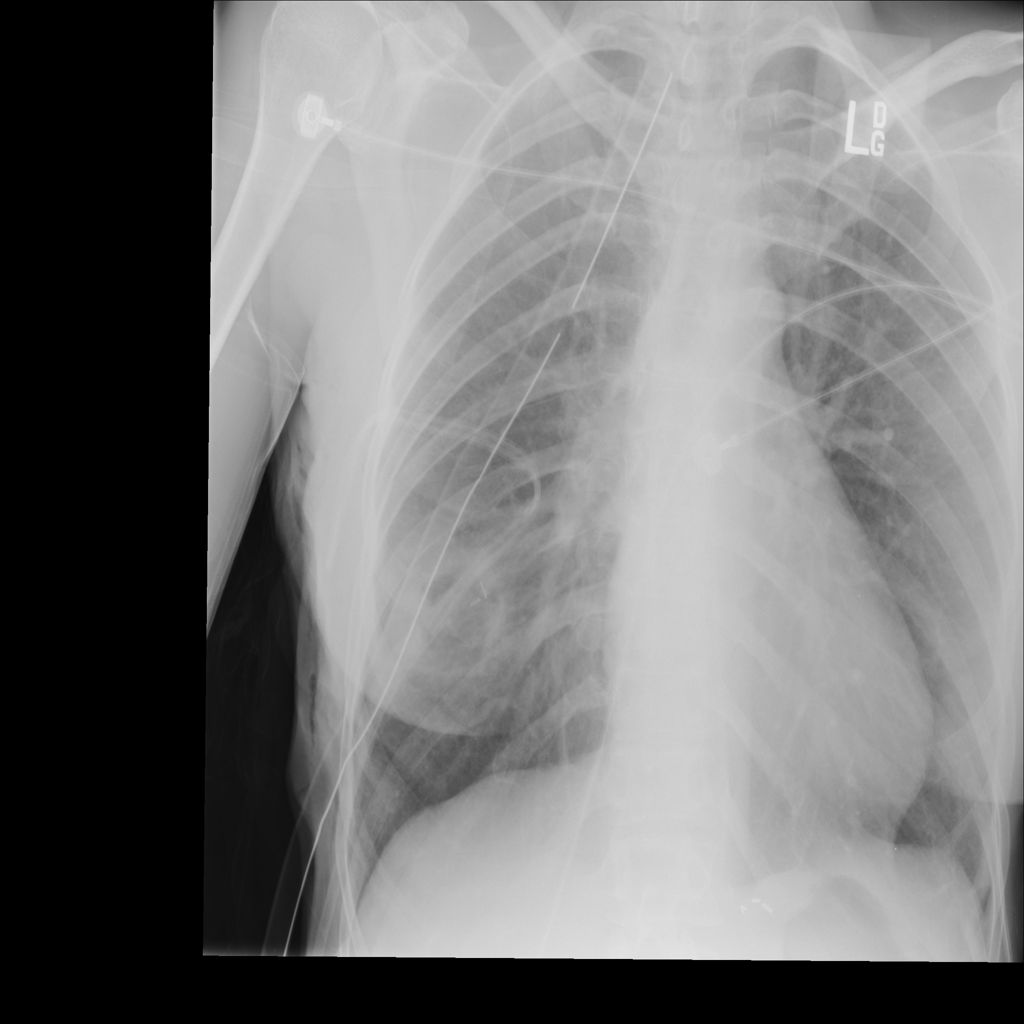

PAT-894B · IMG-000Emphysema

PAT-894B · IMG-000

PA